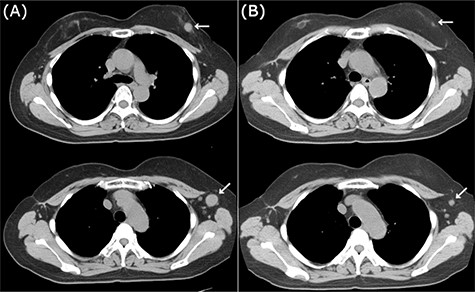

CT images of left breast tumor before and after treatment. (A) Chest CT displaying a nodule in the left breast (top, arrowhead) and lymph node swelling in the left axilla (bottom, arrowhead); (B) Tumors in both the left breast (top, arrowhead, arrowhead) and the axillary lymph node (bottom, arrowhead, arrowhead) shrank after carboplatin and paclitaxel administration.

Because of the early onset of the opposite breast, we administered a combination of carboplatin (area under the concentration-time curve (AUC) 6.0) and paclitaxel (100 mg/m2) every 3 weeks for seven courses. Radiological analysis showed a favorable response (Fig. 5B), and she subsequently underwent breast-conserving surgery with axillary LN dissection. Pathological analysis demonstrated a pCR in the left breast and axillary LNs. She then underwent adjuvant radiotherapy in her left breast. There have been no signs of recurrence 2 years after the treatment.